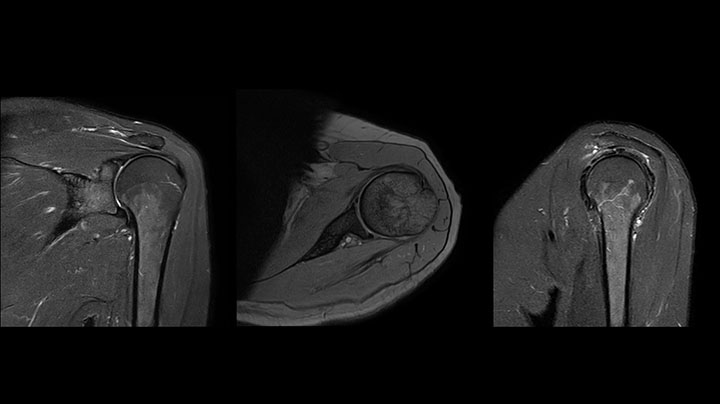

Die Prodiva Schulterspule ist sehr flexibel und hat eine grosse Abdeckung; dies erleichtert eine gute Positionierung, was wiederum zur ausgezeichneten Bildqualität und hohem SNR beiträgt, die wir in unseren Schulteruntersuchungen erreichen.

Scandauer: 2:55 Minuten, FOV: 160 mm, erfasste Voxel: 0,55 x 0,83 x 3,0 mm.

Scandauer: 04:19 Minuten, FOV: 160 mm, erfasste Voxel: 0,55 x 0,80 x 3,0 mm.

Scandauer: 02:50 Minuten, FOV: 160 mm, erfasste Voxel: 0,70 x 0,99 x 3,0 mm.